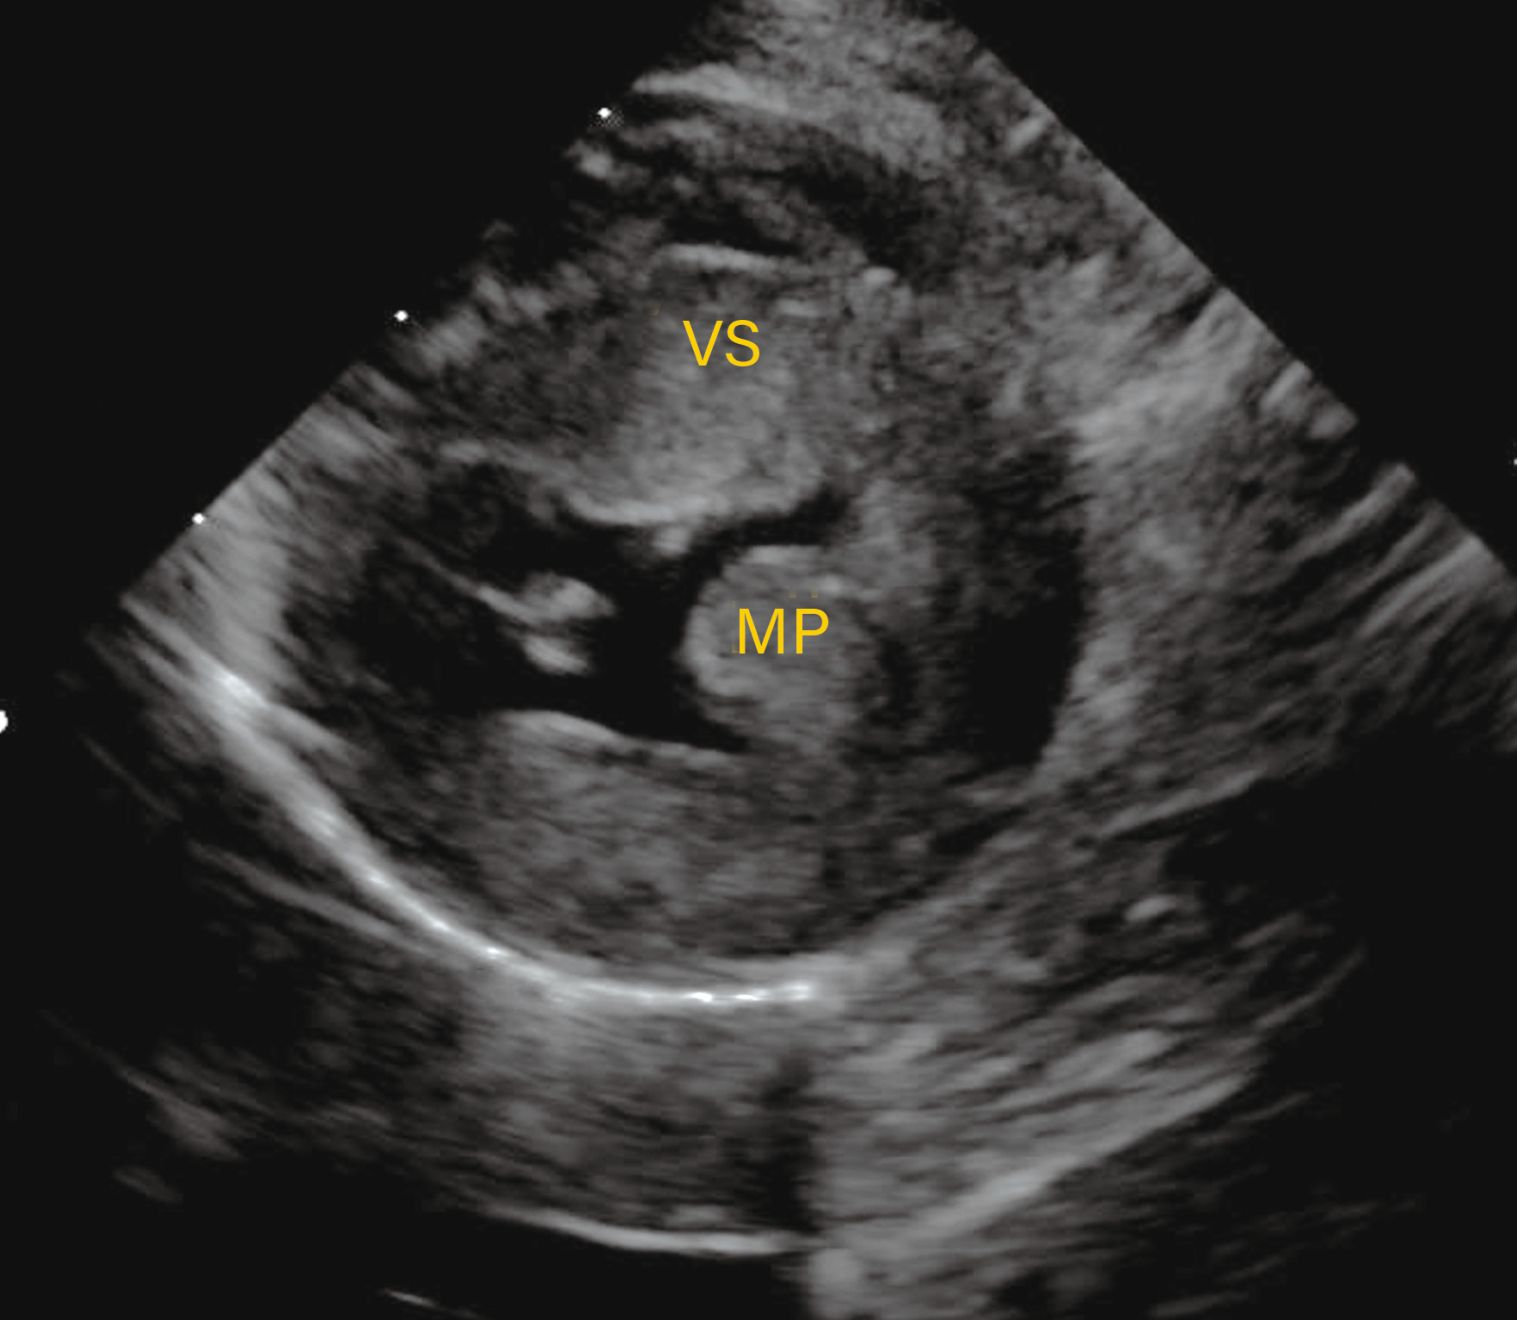

Observațiile ecocardiografice ale HCM pot să prezinte o mare variabilitate.

Figura 2a. Observațiile ecocardiografice ale HCM pot să prezinte o mare variabilitate. Vizualizare parasternală dreaptă în ax lung cu 5 camere prezentând o regiune focală de hipertrofie care afectează septul bazal (*).

Credit: Catheryn Partington Joanna Dukes-McEwan

Observațiile ecocardiografice ale HCM pot să prezinte o mare variabilitate

Figura 2b. Observațiile ecocardiografice ale HCM pot să prezinte o mare variabilitate. Vizualizare parasternală dreaptă în ax scurt la nivelul mușchilor papilari prezentând hipertrofia ventriculară stângă și a mușchilor papilari.

Vizualizare parasternală dreaptă în ax lung cu 4 camere prezentând hipertrofia simetrică a septului interventricular și a peretelui liber al ventriculului stâng.

Figura 2c. Observațiile ecocardiografice ale HCM pot să prezinte o mare variabilitate. Vizualizare parasternală dreaptă în ax lung cu 4 camere prezentând hipertrofia simetrică a septului interventricular și a peretelui liber al ventriculului stâng.

Abrevieri: LA , atriul stâng (AS); LV, ventriculul stâng (VS); Pm, mușchiul papilar